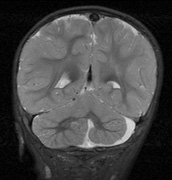

Optic nerve gliomas may involve the optic chiasm and be associated with endocrine disorders or nystagmus.68–70 Surgical excision of chiasmal gliomas (Fig. 6) carries a high risk of visual loss. Invasion of the hypothalamus or the third ventricle carries a poor prognosis, with greater than 50% 15-year mortality rate.71 One review of radiation treatment for chiasmal gliomas collated data from small case series and found no significant long-term improvement in visual function, progression, or mortality with radiation treatment.71 Other reports suggest that radiation doses over 4500cGy improve symptoms and slow progression of chiasmal gliomas over several years.72 Adequate tumor coverage by radiotherapy results in irradiation of normal brain and nearly all children need hormone replacement.73 Chemotherapy is an alternative.74,75

|